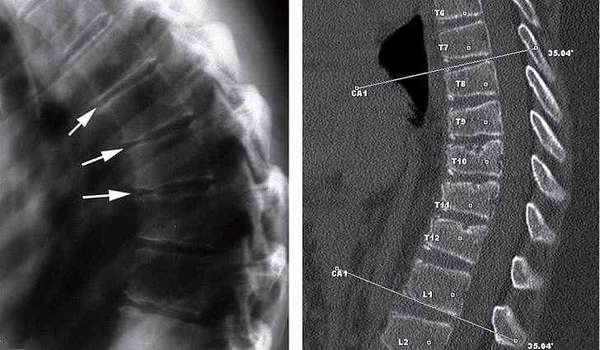

В своем начальном периоде болезнь Форестье рентгенологически практически не отличается от банального спондилеза. Чтобы их дифференцировать необходимо провести рентгенологическое обследование всего позвоночника. Выявление патологических очагов сразу в нескольких отделах позвоночного столба говорит в пользу болезни Форестье. Более информативной является рентгенография позвоночника в боковой проекции. Она выявляет, что гиперостоз происходит не только на уровне межпозвоночных дисков, как при спондилезе или остеохондрозе, но в первую очередь на уровне тел позвонков. Большое значение имеет проведение рентгенологических исследований в динамике. При спондилезе процесс костеобразования сохраняет свой локальный характер и быстро прекращается. Болезнь Форестье отличается длительным течением с постоянным увеличением костных разрастаний. Необходимо также дифференцировать болезнь Форестье от болезни Бехтерева.

В более позднем периоде болезнь Форестье рентгенологически характеризуется массивными костными напластованиями, толщина которых может достигать 1,5 см и сохраняется примерно одинаковой в переделах одного отдела позвоночника. В грудном отделе обычно такие напластования больше выражены справа. В шейном отделе они не образуют сплошную полосу, а располагаются фрагментарно. Поясничный отдел поражается полностью, но изначально костеобразование более выражено в околодисковых областях и слева.

На рентгенограммах позвоночника видно, что по передней поверхности позвонков на уровне межпозвонковых дисков образуются клювовидные выступы, которые, срастаясь между собой, блокируют движения в позвоночнике.

Диагноз болезни Форестье ставится на основании рентгенографии позвоночника, лучше в боковой проекции. Причем необходимо динамическое наблюдение, так как на ранних стадиях эти изменения можно принять за спондилез. Желательно обследовать весь позвоночник, поскольку окостенение может развиваться в различных его отделах, а также быть односторонним.